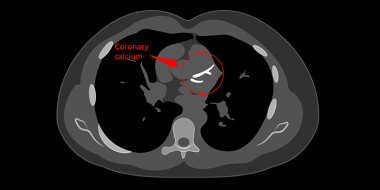

Angina pectoris

In de NHG-Standaard Stabiele angina pectoris (H&W 2004;47:83-95) staat onder het kopje niet-medicamenteuze behandeling een aantal adviezen, zoals stoppen met roken en fysieke training. Deze adviezen stemmen overeen met de eveneens recent verschenen Richtlijn Hartrevalidatie.Hierin is angina…